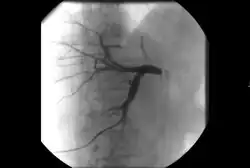

Takayasu arteritis angiography

Dissections can also arise in virtually any other artery. Carotid artery dissection, for example, places patients at increased risk for stroke and may extend further into the blood vessels within the brain. Vertebral artery dissection are less common but also dangerous for similar reasons. Mesenteric artery dissection may limit the blood supply to the intestines. Renal artery dissections can decrease blood flow to the kidneys and contribute to hypertension.[94] Peripheral arterial dissections can be found elsewhere in the arms and legs. These dissections can occur primarily due to focal traumas, underlying vascular disease, or as an extension of a larger, complex aortic dissection that tears further into these smaller branches.